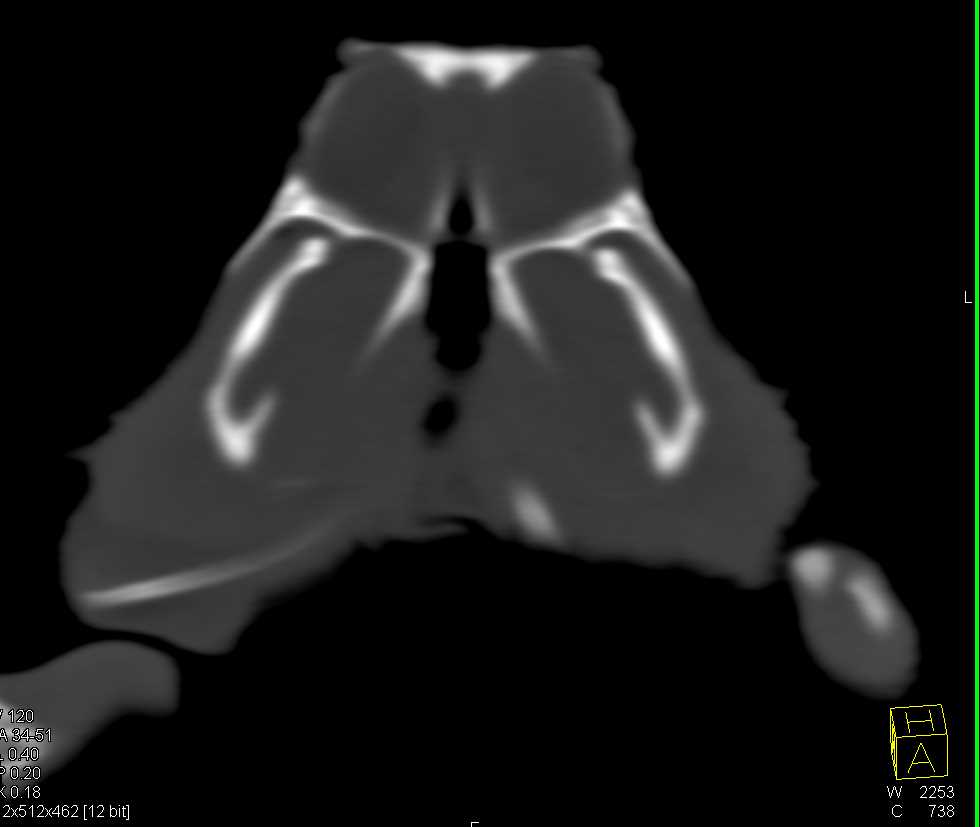

Bearded Dragon